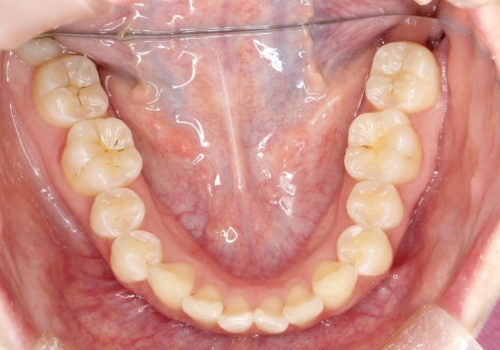

前歯のガタつきを治したい 翼状捻転マウスピース矯正

- 上顎前歯の突出、がたつき(翼状捻転)を主訴に来院されました。当院では総合歯科医療が可能であるため、矯正前処置として虫歯治療・歯周治療、親知らず抜歯を施行しました。その後、非抜歯かつ口元が出ないようなマウスピース治療を行いました。仕事柄、1日の装着時間が短くなってしまう時期もありましたが、患者様と相談しながら問題なく終了しています。